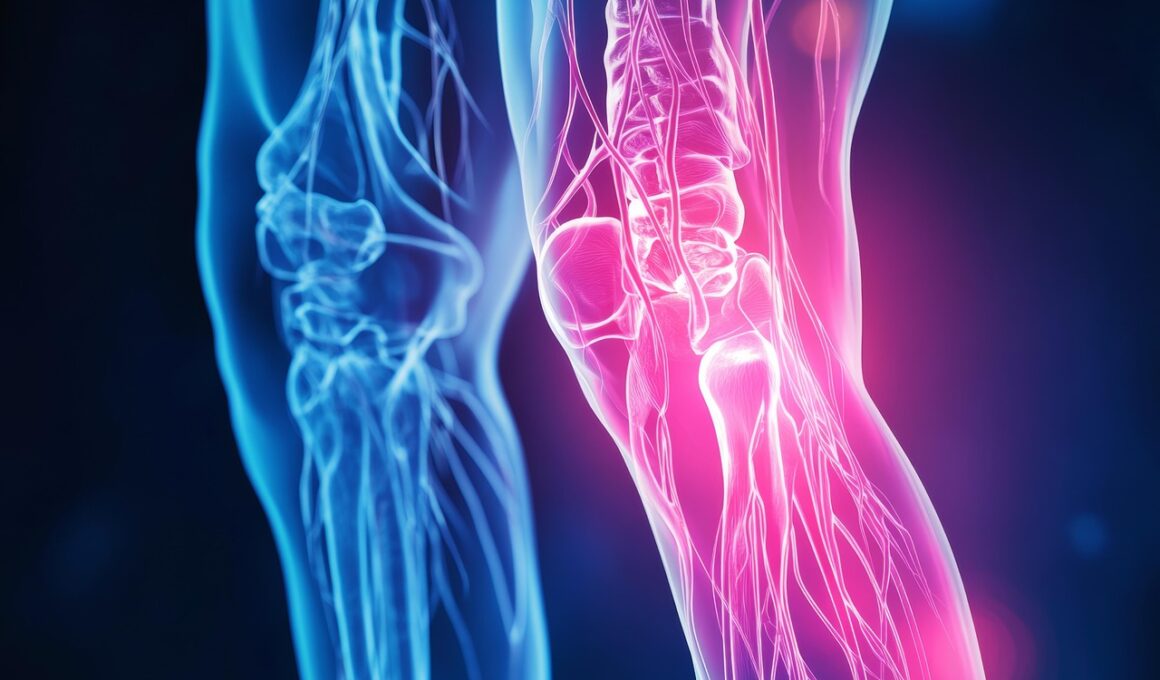

The risk of osteoporosis is notably heightened in elite skeleton athletes due to the intense physical strain they experience. Osteoporosis is a condition characterized by reduced bone density and increased fracture risk. Regular training without adequate hormonal balances can exacerbate this condition, particularly if factors like insufficient nutrition or hormonal fluctuations are present. Female skeleton athletes often face a higher risk when their hormonal levels fluctuate during training cycles. This is crucial because estrogen plays a protective role in bone health. Male athletes, while generally less susceptible, can also face risks if testosterone levels are compromised. Understanding the signs of bone weakness is imperative for all athletes involved in skeleton. Common indicators of lowering bone density include frequent fractures, chronic pain, and changes in physical performance. Therefore, athletes must engage in regular screenings and incorporate preventative measures early in their training. Prevention strategies include resistance training, maintaining healthy body weight, and ensuring adequate intakes of calcium and vitamin D, which are vital for optimal bone health. By recognizing these risks, skeleton athletes can proactively manage their bone health amid the challenges of their demanding sport.

Incorporating strength training is crucial in the pursuit of enhancing bone density among skeleton athletes. This type of physical activity stimulates bone growth and helps counteract the effects of osteoporosis. Structured weight-bearing exercises, such as squats, deadlifts, and resistance training, have profound effects on strengthening bones by promoting new bone tissue formation. By placing stress on the bones during resistance training, skeleton athletes can stimulate the release of growth factors and hormones that enhance bone density. A solid program should be designed to progressively increase load and intensity over time to yield optimal benefits. Additionally, incorporating agility drills and flexibility exercises can improve balance, which is essential in preventing falls or fractures during training and competition. To further magnify bone strength gains, athletes must ensure sufficient recovery time between training sessions, which is when the body repairs and strengthens bone. Thus, implementing a well-rounded training routine that includes resistance training, adequate rest, and nutrition can significantly impact the skeletal health of skeleton sport competitors, ensuring that their performance remains resilient against the physical challenges of the sport.

Monitoring hormonal health is essential for skeleton competitors in maintaining bone integrity. Regular assessments can assist in identifying potential hormonal imbalances that may arise from intense training or lifestyle factors. Hormonal changes, especially fluctuations in estrogen and testosterone levels, can occur due to overtraining, inadequate nutrition, and stress. Establishing a baseline for hormonal levels allows athletes to understand their unique profiles and adapt their training and nutrition accordingly. Monitoring methods may include blood tests and professional evaluations to analyze hormone levels. Athletes should also be conscious of other health markers, such as bone density assessments through DEXA scans, which provide insights into bone strength and density changes over time. By combining hormonal health evaluations with practical strategies, athletes may proactively manage their bone health, minimizing the risk of injury. Collaboration with healthcare professionals can also provide guidance in creating a comprehensive preventive strategy tailored to individual needs. Furthermore, educating oneself about the signs of hormonal imbalances supports athletes to be proactive in their health, ensuring long and fruitful careers in their demanding sports while safeguarding their skeletal health.